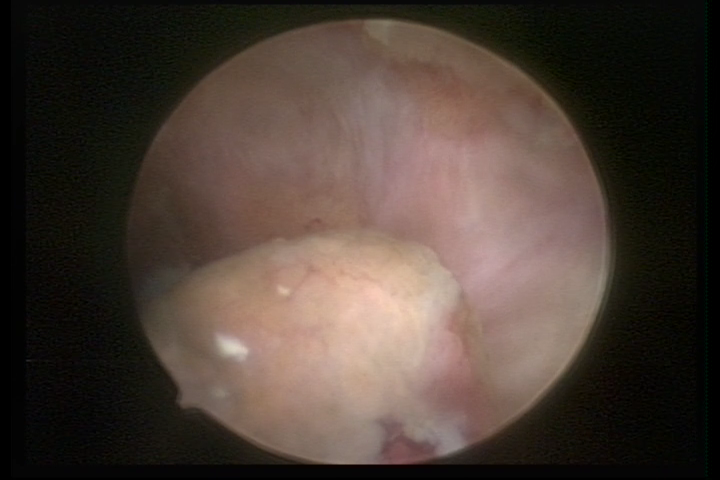

It may present a variable range of macroscopic aspects, with a pseudolopypoid aspect; resembling cerebroid tissue or presenting a decidual reaction; superficial vascularization is more evident presenting vessels in the shape of corkscrew or spirals also viewing the vascularization with atypias, with an increase on the thickness of the superficial vessels, tissue in necrosis and small dendrites (papillomatous) may be found.